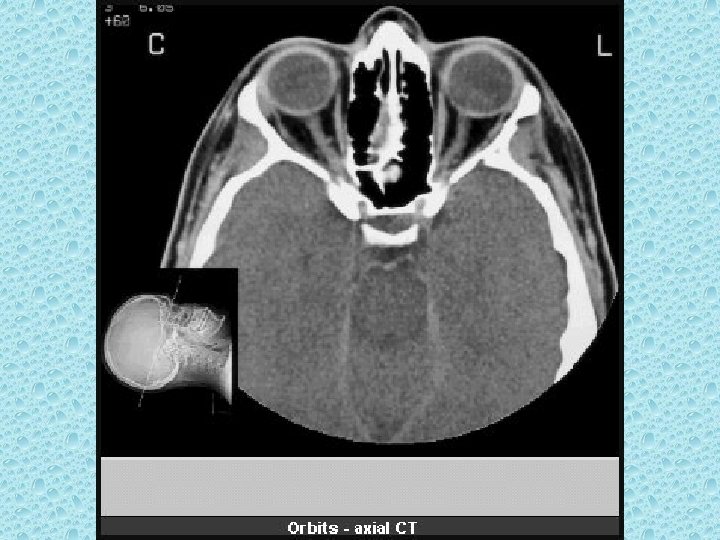

ORBİTAYI OLUŞTURAN KEMİKLER • • • Frontal Sfenoid Maksiller Zigomatik Lakrimal Etmoid

ORBİTA İÇERİSİNDEKİ YUMUŞAK DOKULAR • Bulbus okuli • Palpebralar • Rektus kasları: Medial, lateral, süperior, inferior, süp oblik inferior oblik ve levator palpebra kası • Optik sinir • oftalmik ven • Retrobulber yağ dokusu

GÖZ KÜRESİNDEKİ YAPILAR • • Sklera Konjuktiva Ön kamera Arka kamera Lens Vitreus Retina ve koroid tabaka